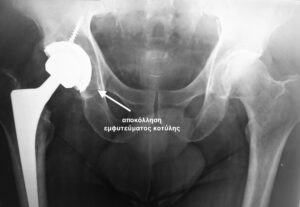

- Ακτινογραφία που εκ πρώτης όψεως δείχνει να μην έχει σοβαρό πρόβλημα, όμως έχει τεράστιο περιπροθετικό κάταγμα της κοτύλης. Έχει αποκολληθεί το εμφύτευμα από τη θέση του και έχει αποσπασθεί μαζί με ολόκληρο το οστικό οπίσθιο τοίχωμα της κοτύλης

- Τρισδιάστατη αξονική τομογραφία (παράσιτα λόγω εμφυτεύματος) δείχνει την αποκόλληση του εμφυτεύματος της κοτύλης και την οπίσθια μετατόπιση του , μαζί με το κάταγμα του οπισθίου τοιχώματος της κοτύλης.